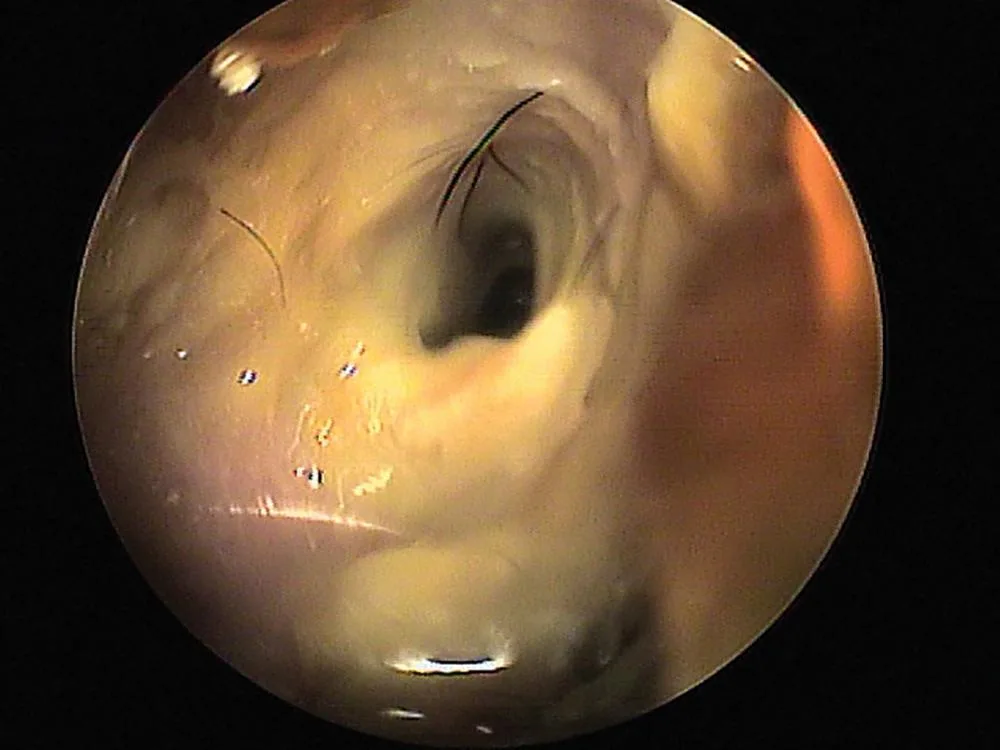

Figure 1 Otitis externa resulting from Pseudomonas aeruginosa infection. Severe biofilm formation, often seen with this organism, is present.

A close-up view of an endoscopic examination of a canine ear canal, showing the inner structures including the tympanic membrane and surrounding tissues. Fine hairs and debris are visible within the canal, indicating potential irritation or infection.